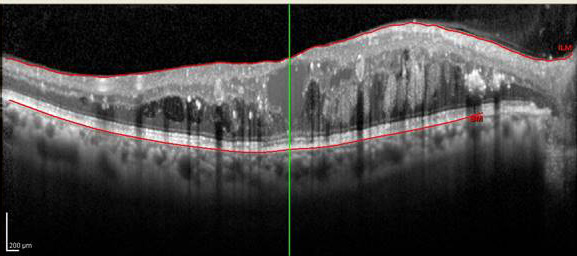

Konfluente MicroPulse® Behandlung inklusive Fovea

Die „Target Cell“ Technologie im Pattern Scanning Mode garantiert dem Behandler beste Visualisierung der zu behandelnden pathogenen Netzhautstrukturen, obligat bei einer unterschwelligen MicroPulse® Behandlung, und ein Garant für optimale klinische Ergebnisse.